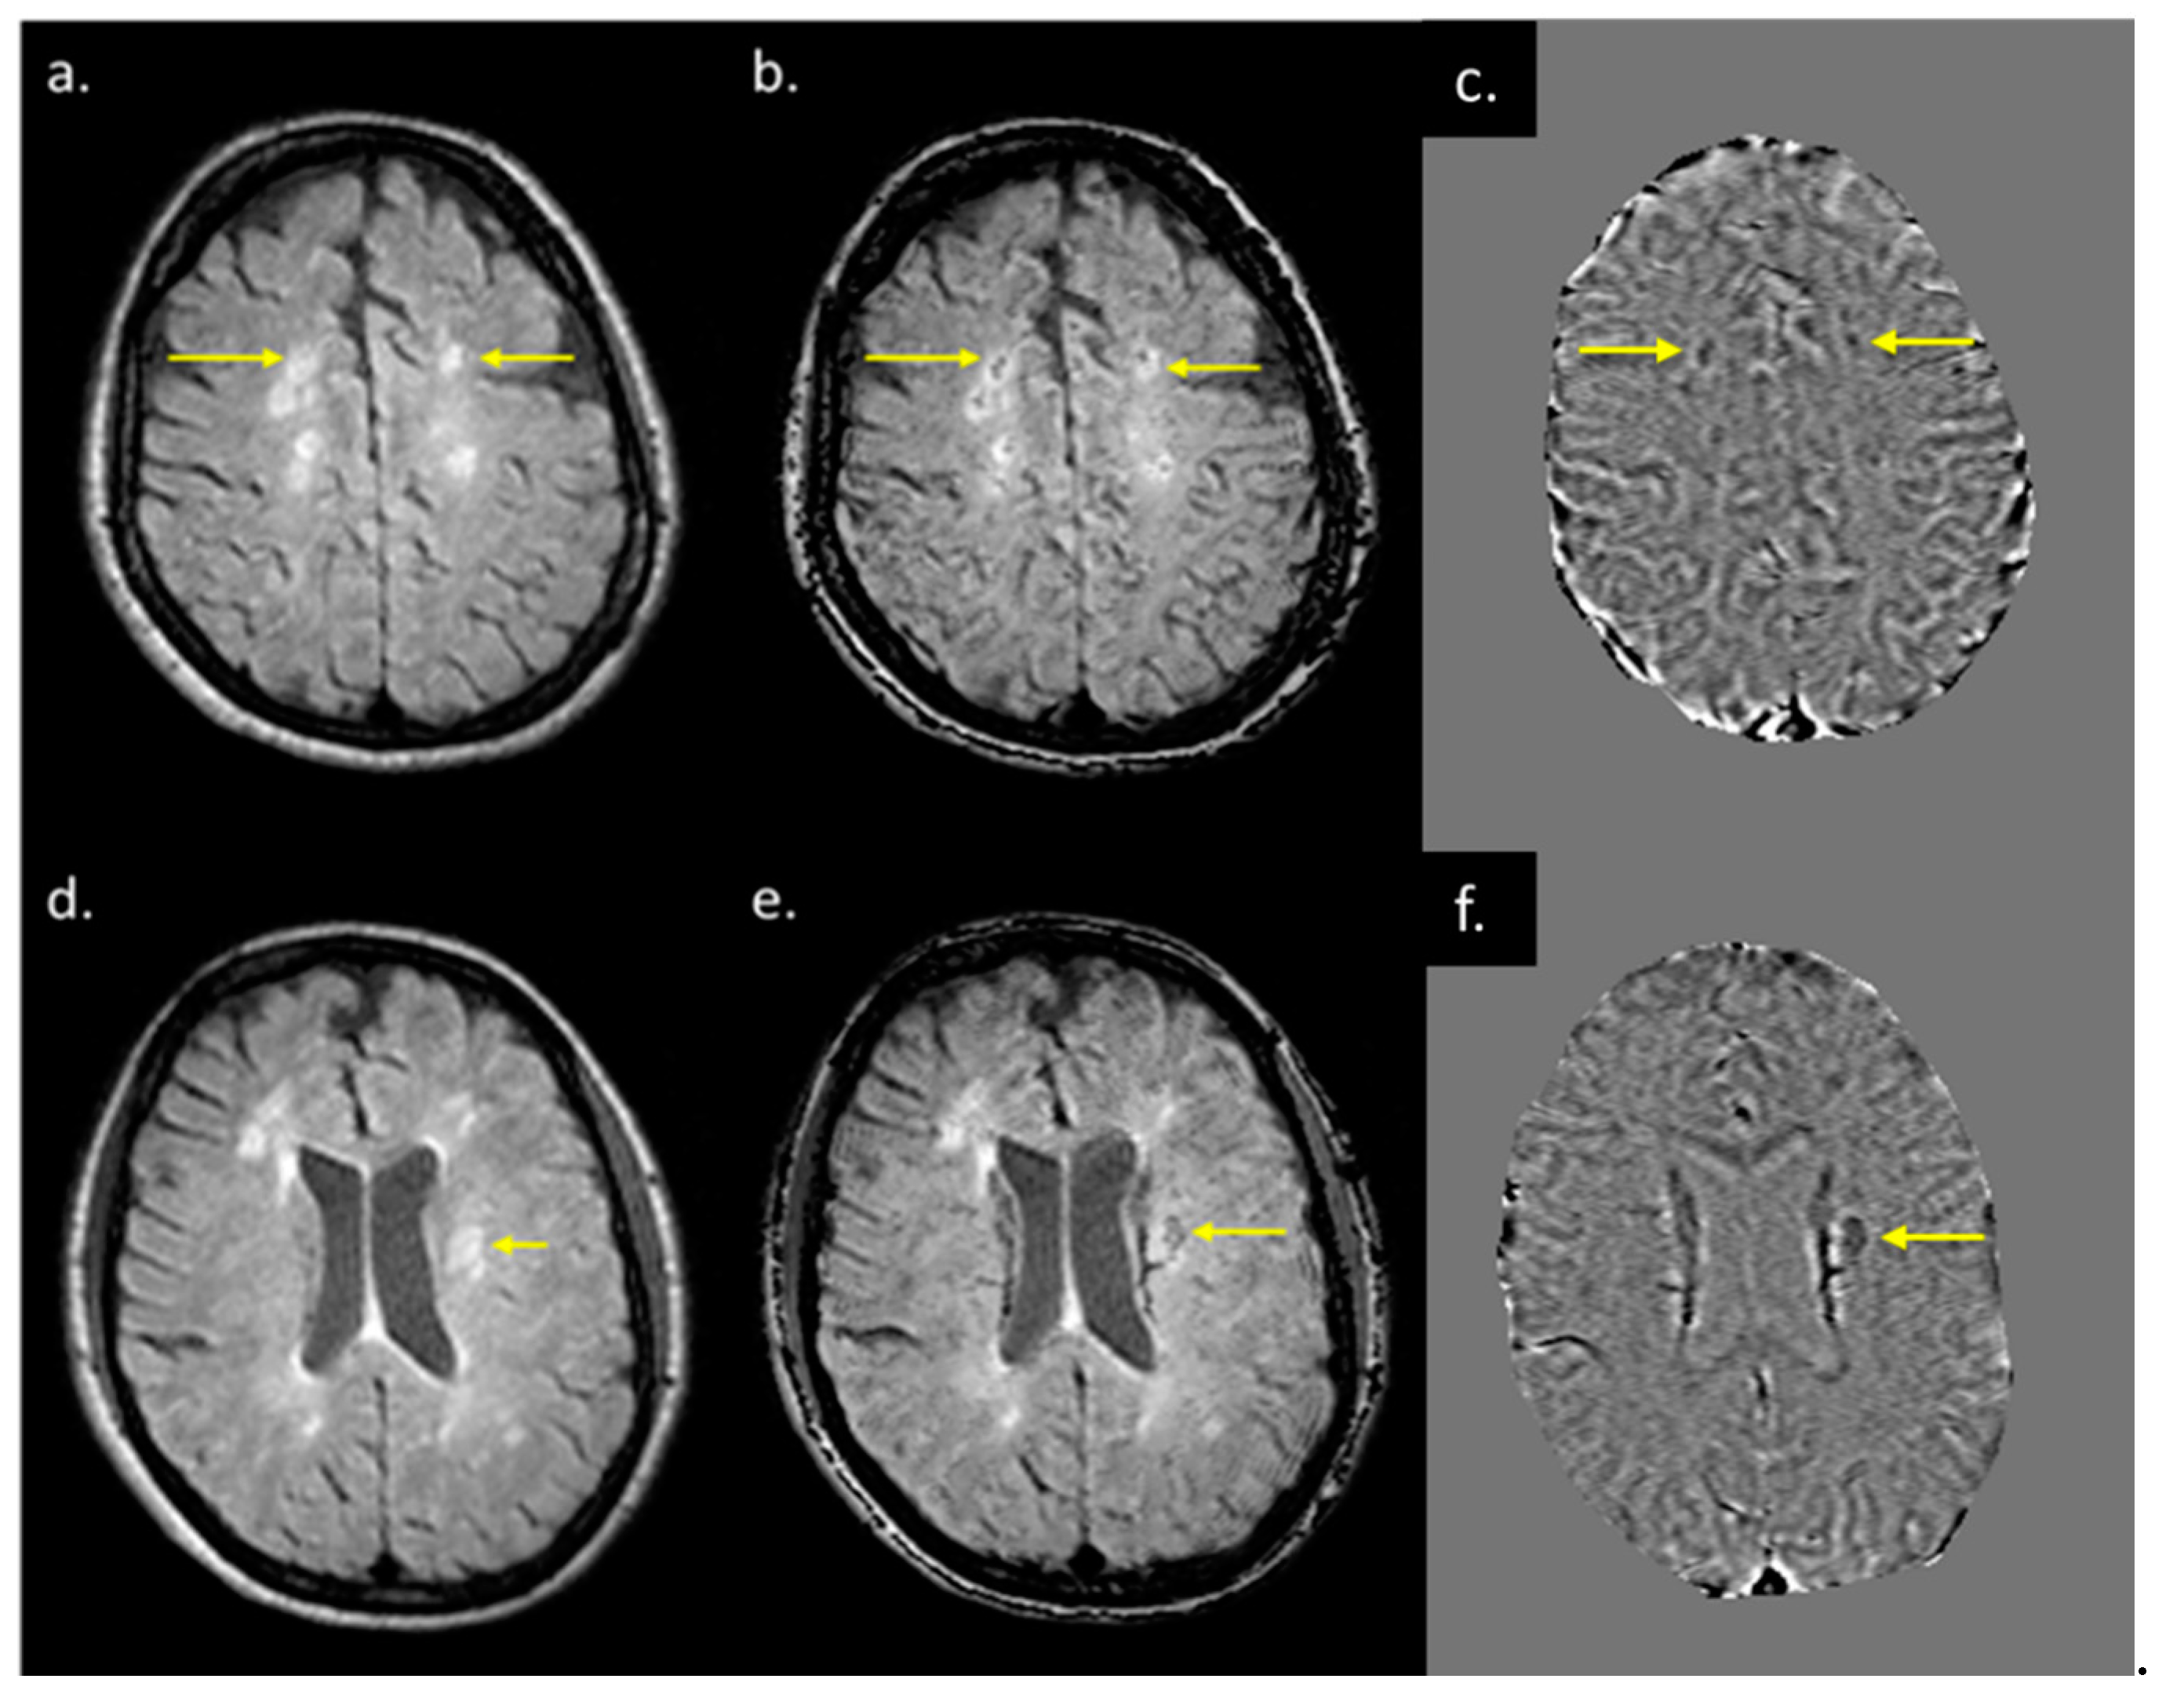

3.3. QSM ± Lesions

3.5. Correlation between Different Imaging Sequences